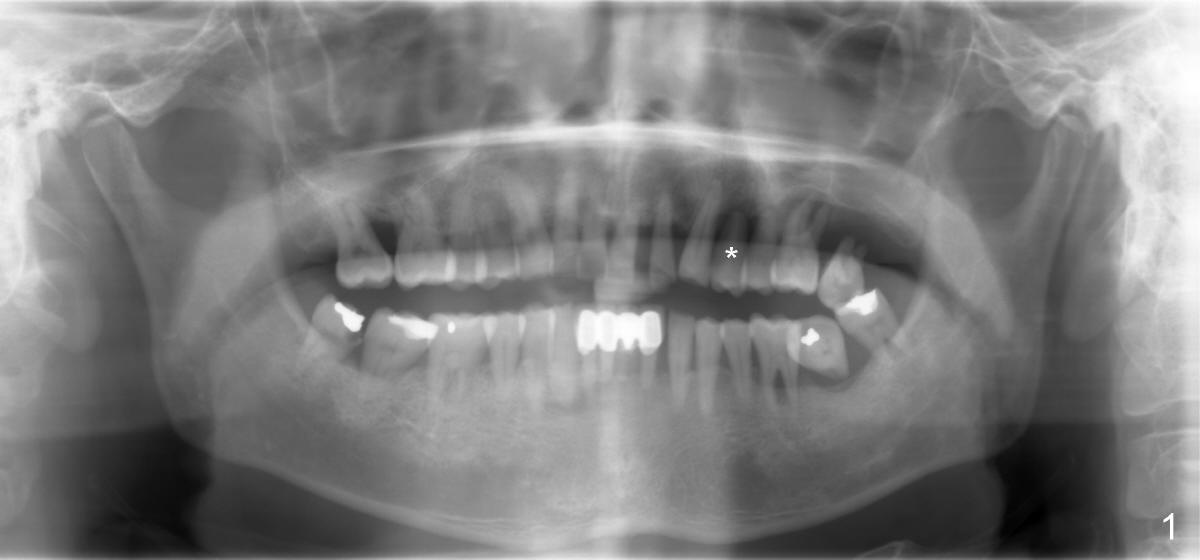

Dear Dr. Borgner: This Friday I may try D implant in a 50-year-old perio patient in #12 (Fig.1 *, Fig.2 is magnification of Fig.1 with sinus floor pointed by arrowheads), which was extracted ~ 1 month ago. PAs were taken yesterday (Fig.3). The socket must be partially empty. Can we start with RT2 or D1 spreader before using D2 one? #15 appears to be unnecessary. Tuesday, June 25, 2013 6:40 AM

Dr Wei, This is exactly what we spoke about in the class. 1- You can go right to the D2 channel former turned 90 degrees (Fig.4: design of D2 implant turned 90 degree). 2- Engage all of the apical bone you can without entering the sinus. 3- Do not remove any bone with a bur in order to not remove any remaining interseptal bone ! 4- Place a D2 implant as directed previously. This should work perfectly if you follow these steps. Dr Borgner Thursday, June 27, 2013 2:32 PM